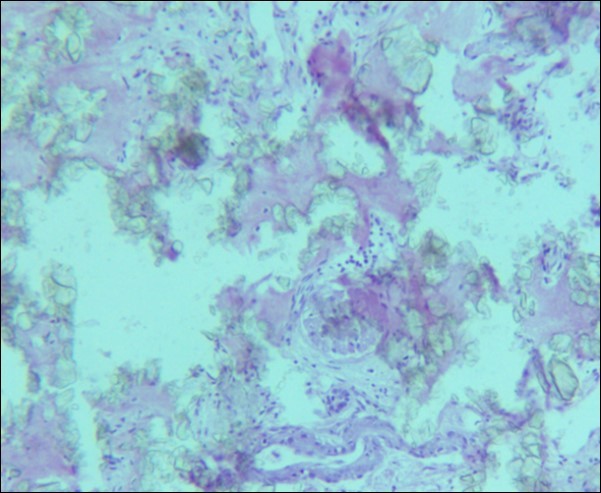

A 30 years old male, resident of Lahore was admitted for opinion regarding the necessity for regular hemodialysis after rejection of second renal transplant. Family history was suggestive of hereditary disease as two of his sisters had died of nephrocalcinosis leading to chronic renal failure at the age of 4 years. Consanguineous marriages in past many generations were also reported. Three cousins of the patient had recurrent stones with normal kidney functions. His past history revealed retention of urine at the age of 5 years due to stone in urethra. Patient presented again after 20 years in 2008 with retention of urine which was relieved by catheterization. Renal ultrasound and X ray KUB reported normal kidneys in both instances. Work up for stone formation was not undertaken at that time. The patient was put on hemodialysis and was planned for transplant which was undertaken in May 2009. After one month, follow up tests revealed Serum Creatinine to be 2.0 mg/dL. Renal Biopsy done in Sep 2009 revealed rejection of transplant. Hemodialysis was started and a second transplant was contemplated. Hemodialysis continued for 2 years till Dec 2011 when second transplant was carried out. A repeat renal biopsy was indicated for increasing serum creatinine. Again transplant rejection was evident on histology. Further investigations revealed Urinary oxalate excretion exceeding 40 mg/day (30 mg Oxalate/gram creatinine). His Blood investigations at the time bone marrow studies revealed bicytopenia with a Haemoglobin of 7.8g/dl, White blood cell count of 5.8 x 109/l; Platelet count of 120 x 109/l. Serum Creatinine was 3.6mg/dl. An attempt to correct the cytopenias by iron, vitamin B12 and folic acid supplements met with failure. No response to anemia could be elicited by adding erythropoietin to the treatment regimen. Renal and bone marrow biopsy were undertaken. Renal biopsy of the patient revealed crystals of calcium oxalate in the tubules (Figure 1). The same crystals were also visualized in bone marrow aspirate (Figure 2a and Figure 2b) and trephine biopsy (Figure 3).

Figure 1.Photomicrograph of renal tissue from case I with a preserved glomerulus and clusters of oxalate crystals in the tubules.